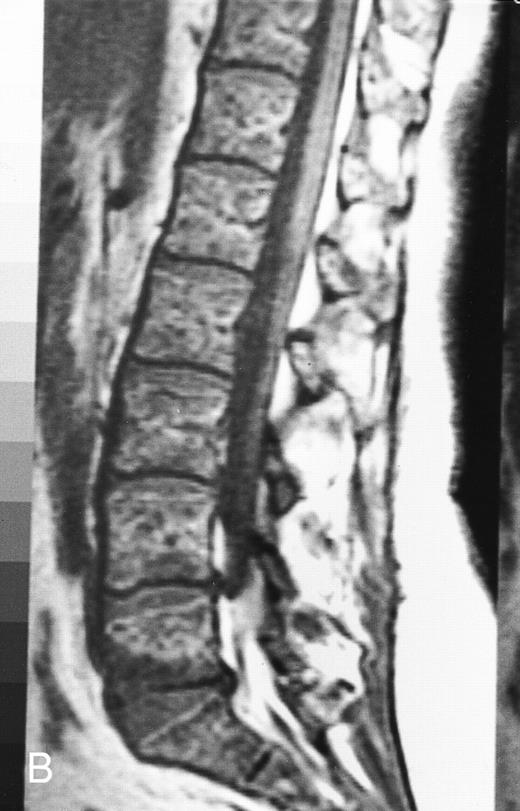

Normal appearance of spinal bone marrow in a 45-year-old woman: T1-weighted (500/11, TR/TE) (A) and T2-weighted, fat-suppressed fast spin echo (4000/96, TR/TE, ET 16) (B) sagittal MR images of the lumbar spine. Note increased signal of the vertebral bodies, relative to the intervertebral discs in (A) and increased deposition of fatty marrow around the basivertebral veins (arrowheads). On the T2-weighted image, normal intervertebral discs are brighter than the vertebral bodies; low signal in the L4-L5 and L5-S1 discs is due to degenerative changes (arrows).